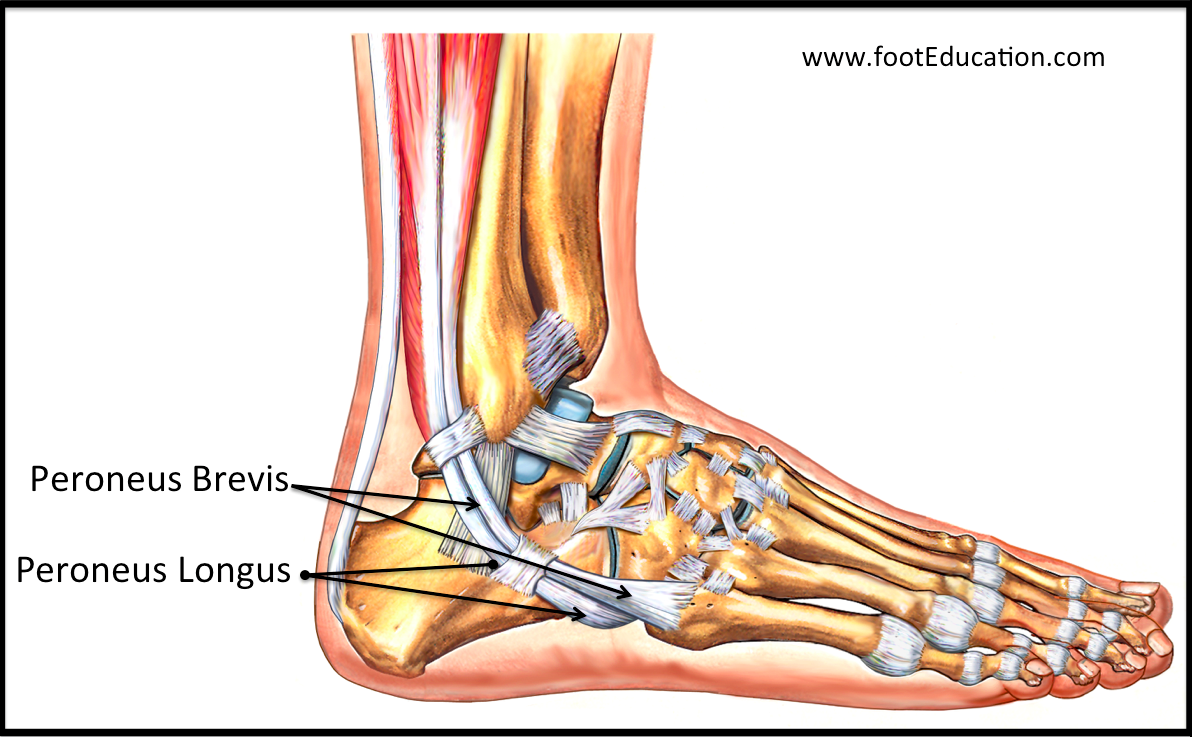

Peroneal tendonitis store, Peroneal Tendonitis FootEducation store

Peroneal Tendonitis FootEducation

Peroneal Tendon Attenuation Peroneal Tendonitis SLO Motion